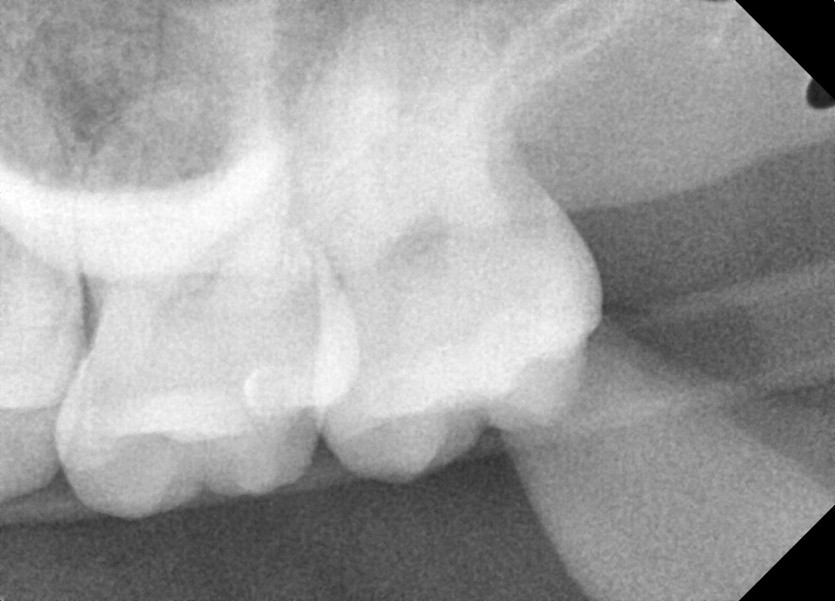

#18,28,38,48 사랑니 발치

구강 외과 전문의가 당일 발치했습니다.